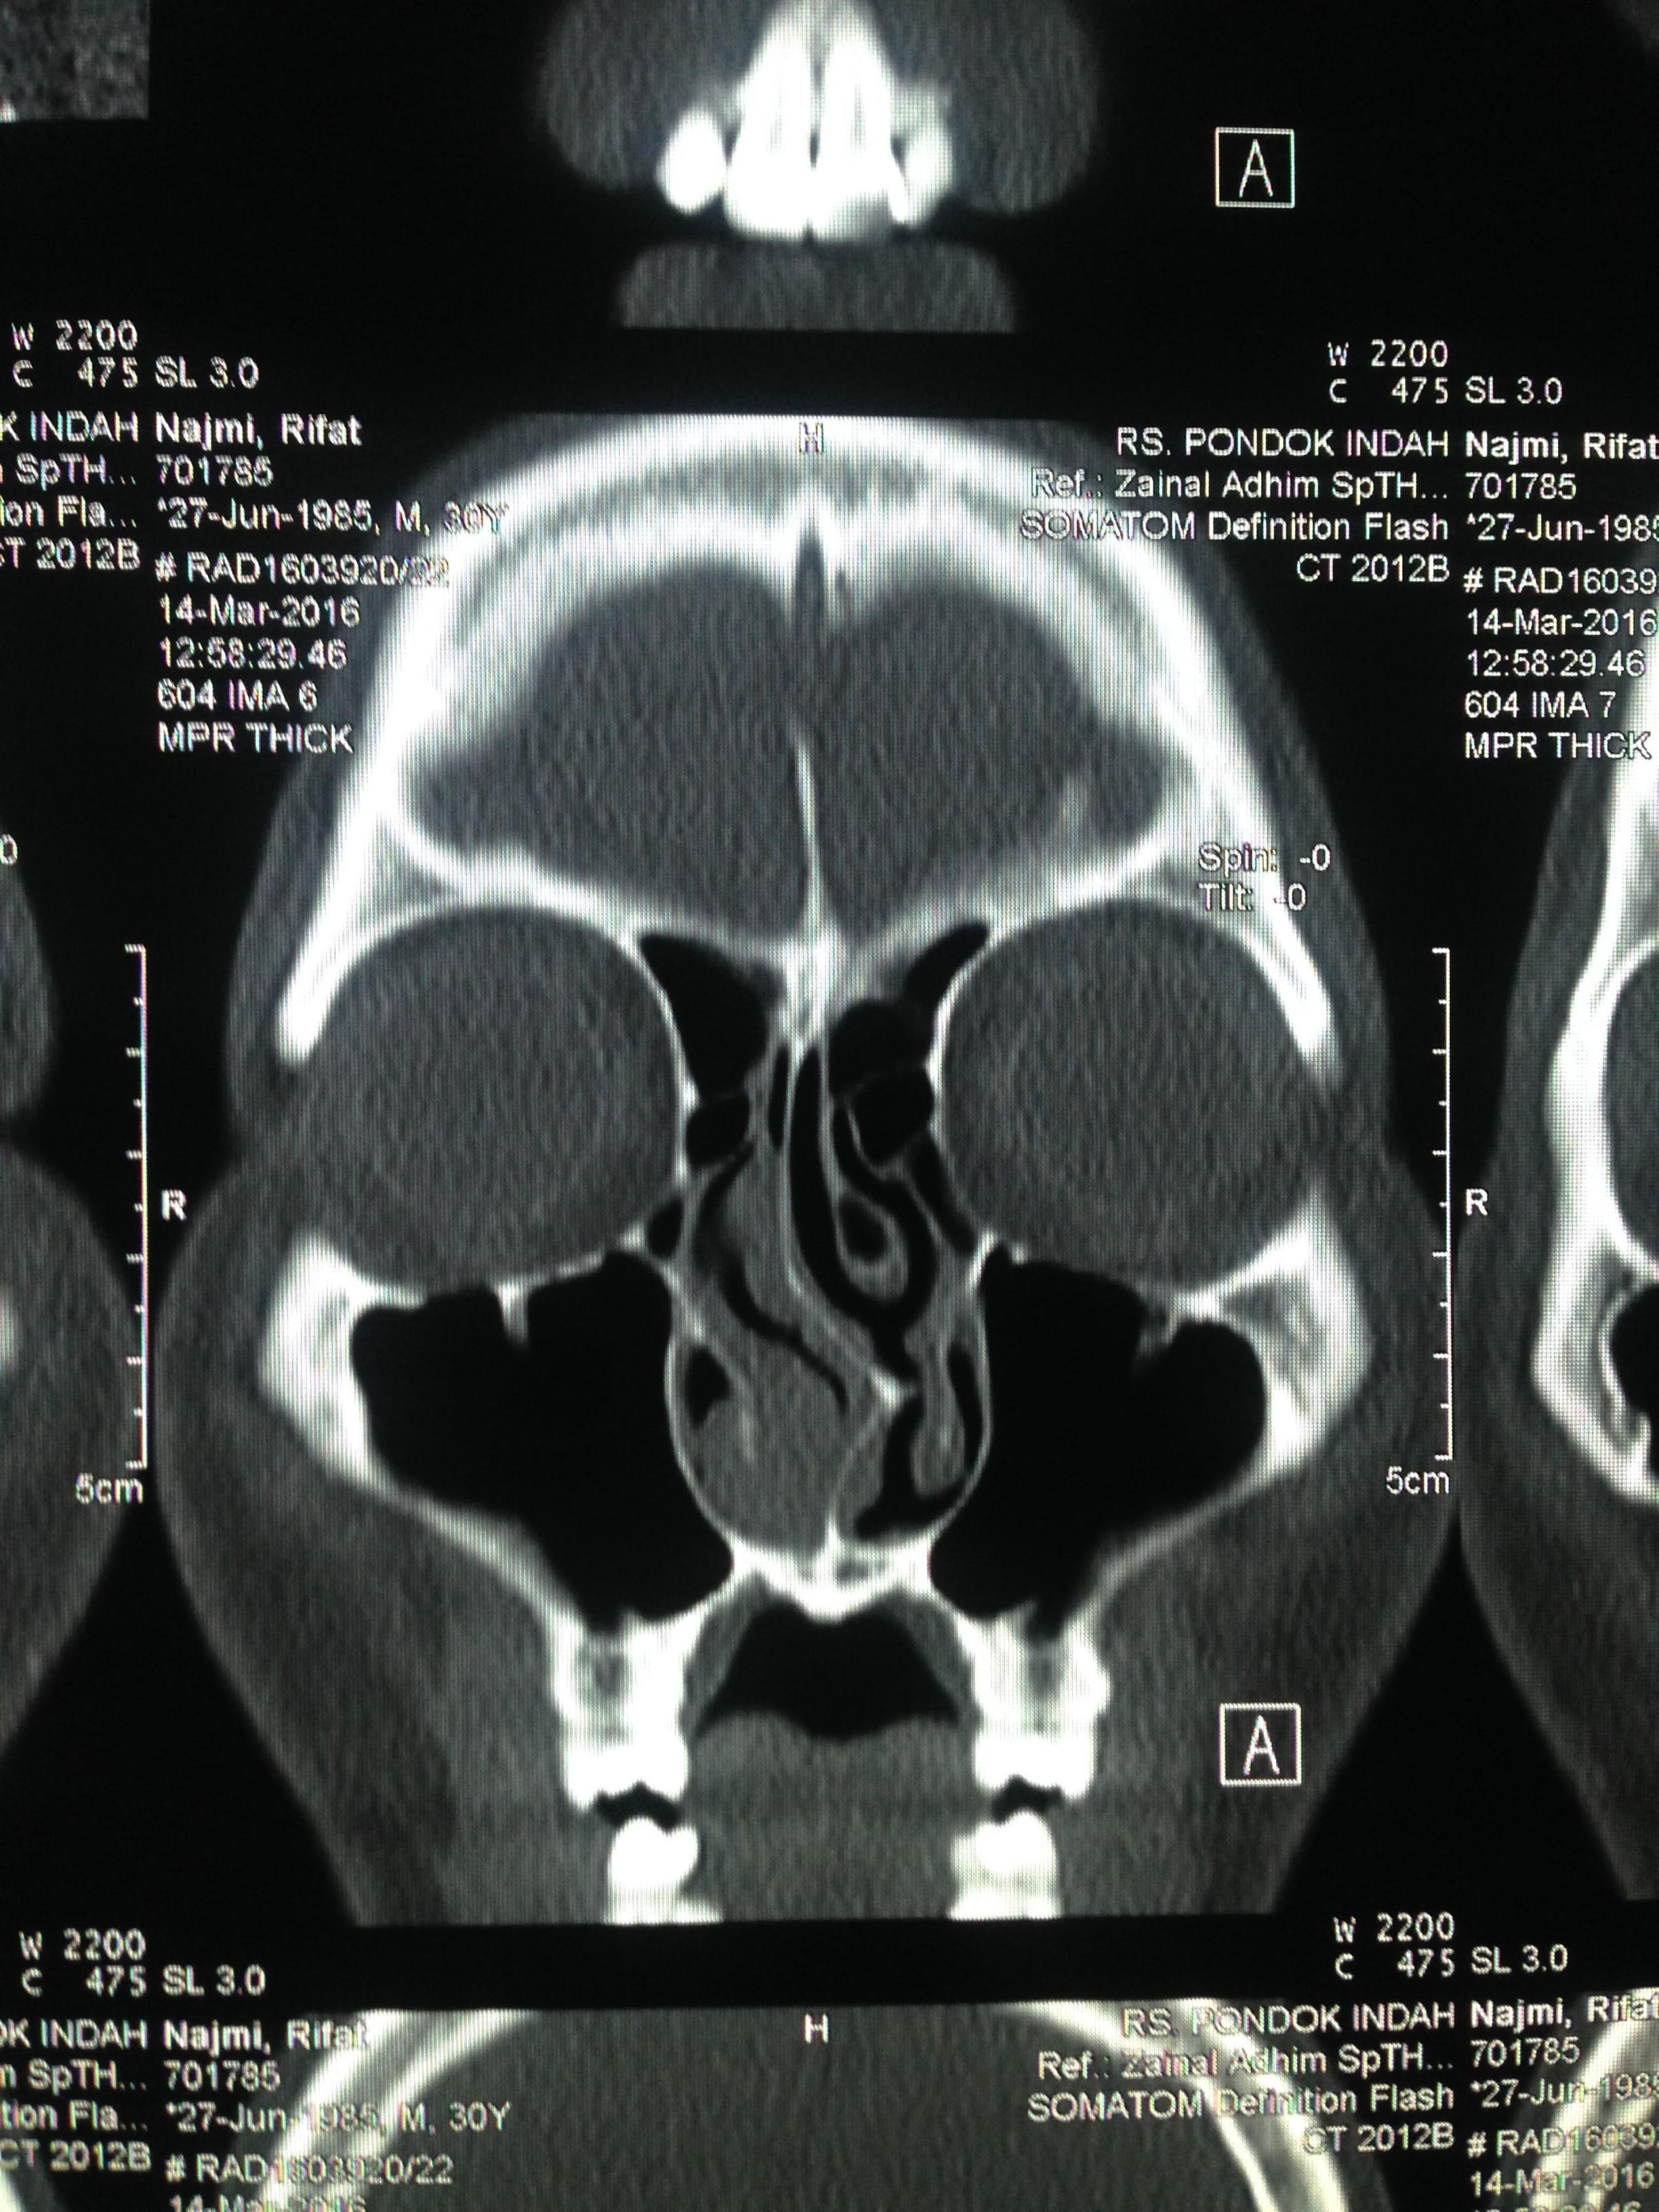

Faktor yang menentukan besaran biaya antara lain bagian tubuh pasien yang menjalani pemindaian dan kelas perawatan pasien. Biaya ct scan kepala sangatlah bervariasi dari satu tempat ke tempat lainnya. 1.000.000 hingga lebih dari rp. Agar tidak perlu melalui sederet pemeriksaan yang mungkin cukup 'menyiksa' tersebut, sebenarnya ada banyak hal yang bisa dilakukan guna merawat dan menjaga kesehatan hidung. Ct scan atau mri digunakan untuk memperoleh gambaran area sinus dan hidung secara detail, seperti kondisi peradangan atau penyumbatan yang sulit terdeteksi dengan endoskopi. Biaya ct scan di setiap rumah sakit bervariasi dari rp 1 jutaan. Tes diagnosis ini umumnya tidak dilakukan untuk mendiagnosis sinusitis kronis. Biaya untuk melakukan rontgen tht bervariasi, tergantung dari rumah sakit yang menyelenggarakannya.

Judulnya sih kunjungan akhir tahun, tapi aku baru sempat menuliskannya di awal tahun baru ini. Tes diagnosis ini umumnya tidak dilakukan untuk mendiagnosis sinusitis kronis. Endoskopi pengertian kegunaan dan biaya honestdocs. Contohnya saja untuk harga ct scan kepala di siloam dapat mencapai antara rp 1.350.000 hingga rp 1.500.000 per … Besaran biaya yang dibutuhkan untuk melakukan ct scan bervariasi tergantung dari rumah sakit, kelas perawatan, dan bagian tubuh yang akan diperiksa. Biaya ct scan kepala sangatlah bervariasi dari satu tempat ke tempat lainnya. Di rumah sakit swasta di indonesia, biaya prosedur ini dapat dimulai dari rp. Kompleksnya bagian yang masuk dalam area scanner tersebut, maka anda tidak perlu kaget jika ternyata harga ct scan kepala sangat mahal. Biaya bisa berkisar mulai dari rp. Biaya ct scan di setiap rumah sakit bervariasi dari rp 1 jutaan. Berapa kisaran biaya ct scan. Ct scan atau mri digunakan untuk memperoleh gambaran area sinus dan hidung secara detail, seperti kondisi peradangan atau penyumbatan yang sulit terdeteksi dengan endoskopi. Secara garis besar, tahapan ct scan adalah sebagai berikut ini.